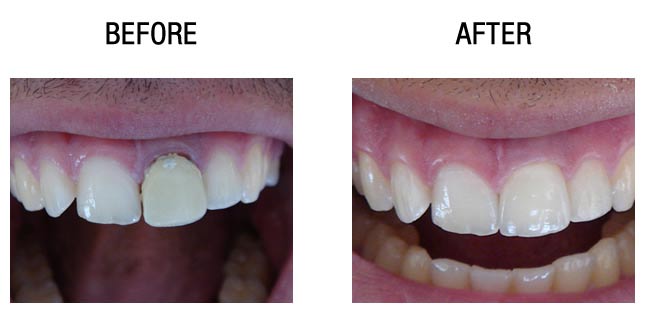

种植牙前后对比

种植牙前后对比

而种植牙,是指在牙骨内打入金属牙根,等到金属牙根与进行牙齿修复的患者本身的牙槽骨进行紧密相结合后,在其牙根位置再装上假牙的一种牙齿修复方法。这种种牙效果稳固,使用期限长,受到很多牙齿修复患者的喜爱。

总的来说种植牙的优点就是:不是真牙好比真牙,稳定牢固,安全无不良反应,使用寿命可达40年以上。